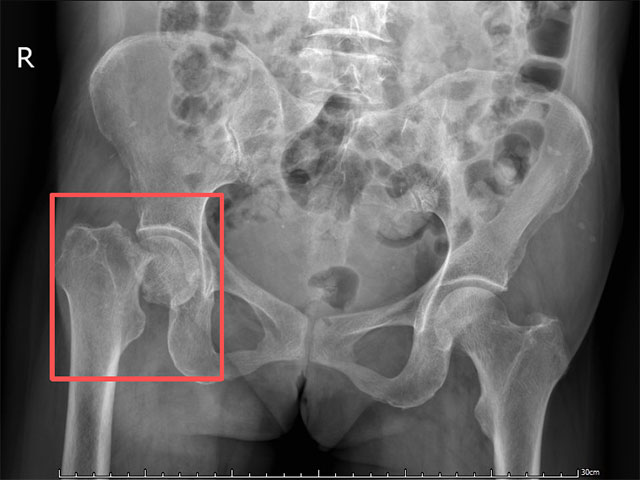

急诊医生迅速为李阿姨安排髋部CT检查,结果提示右侧股骨颈骨折——这是中老年人常见的骨折类型,若治疗不及时,可能影响髋关节功能,甚至导致股骨头坏死。为进一步治疗,李阿姨被急诊以 “右股骨颈骨折”收入骨伤科关节・足踝组。

考虑到李阿姨年龄较大,若采用保守治疗或切开复位内固定术,术后恢复周期长,且可能面临骨折不愈合、股骨头坏死等风险,急诊医生将其以“左股骨颈骨折” 收入骨伤科关节・足踝组进一步治疗。

术前